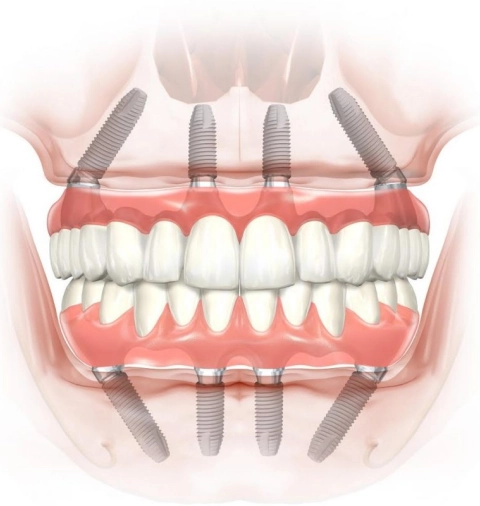

Все элементы внутрикостной дентальной системы имплантации Straumann идеально подогнаны друг к другу. Абатменты сконструированы так, что коронка размещается максимально плотно без щелей и зазоров между ней, десной и имплантатом. Это предупреждает образование кармана, где могут скапливаться остатки пищи и бактерии.